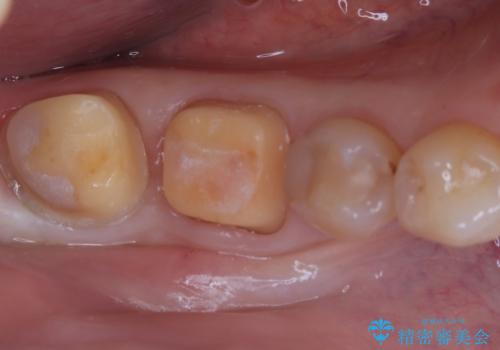

欠けやすい大きなプラスチック充填から、耐久性の高いセラミッククラウンへ

診査の結果、以前治療したCR(コンポジットレジン:プラスチックの詰め物)が広範囲にわたっており、残っている自分の歯との境界から大きく破損している状態でした。奥歯は非常に強い咬合力がかかる場所であり、同様のCR修復では再発や歯根破折のリスクが高いと判断。今回は歯全体をしっかりと保護し、長期的に安定させるために、セラミッククラウンを用いた修復計画を立案しました。

自然な仕上がりとなり、機能・審美ともに改善されました。適合精度が高いセラミックにより、汚れが付きにくく、二次的な虫歯を予防する健やかな環境が整いました。